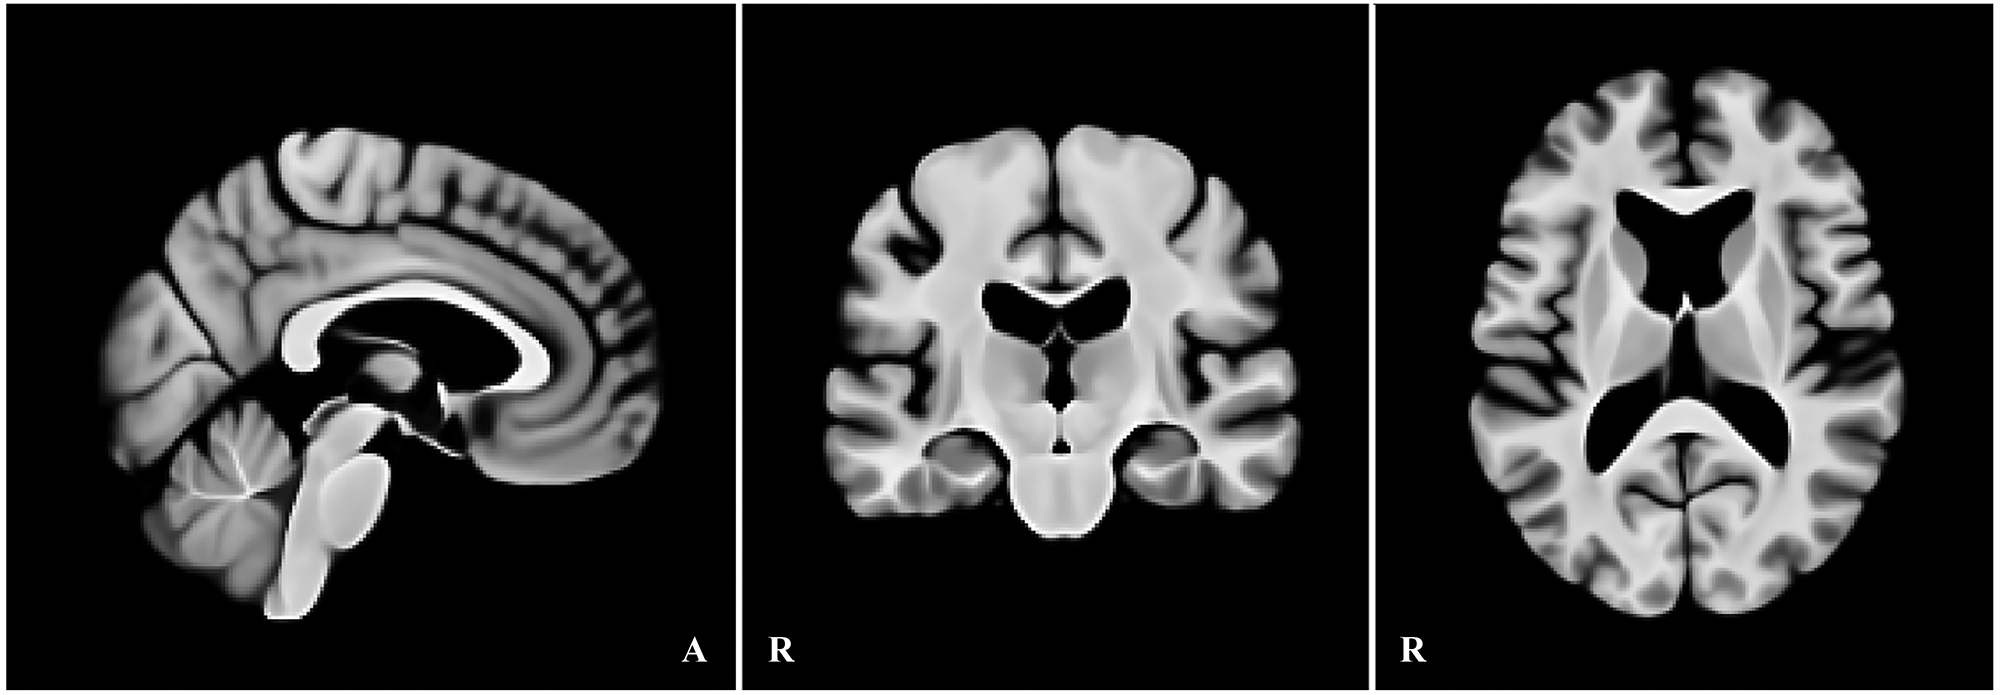

画像:高齢者向け標準脳テンプレートの三面図(矢状・冠状・軸位、1 mm等方)

本研究では、加齢に伴う形態変化――特に拡大した側脳室や皮質の萎縮――を前提に、高齢者の脳画像を適切に基準化できる高齢者向け標準脳テンプレートを作成しました。2020年国勢調査に基づく日本の高齢者の男女比と年齢分布を考慮し、標準脳の構成が実情を反映するよう設計しています。作成データとして OASIS-1 の高齢者 90 例、検証データには IXI の 282 例を用い、従来広く用いられている MNI152 と比較しました。

前処理ではバイアス補正(N4)、強度正規化、頭蓋外除去を行って、各画像データの条件を統一しました。整合(登録)は段階的に実施し、まず剛体変換(6 自由度)とアフィン変換(12 自由度)で大域的な位置・形の差を補正したのち、ANTs(SyN) による非線形変換で微細整合を行いました。CC・MSE・SSIM の収束を確認しつつテンプレートを構築し、最終解像度は 1 mm 等方としました。

検証では、IXIの各画像データを上記の手順で作成した高齢者向けテンプレートと MNI152 の双方に同条件で登録し、全脳の整合(CC/MSE)と皮質下の領域(尾状核・海馬・視床・扁桃体)の一致度(Dice 係数)を評価しました。その結果、60 歳以降で整合が明確に向上し、CC は上昇、MSE は低下しました。特に、拡大した側脳室の位置合わせが安定し、加齢に伴う形態をより正しく反映できることが示されました。さらに、皮質下の各領域ではDice 係数が 1~4%向上し、局所の位置合わせ精度も改善しました。